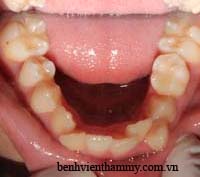

Trường hợp bệnh nhân người lớn - Răng mọc chen chúc niềng răng không nhổ răng:

(Hình ảnh trước điều trị)